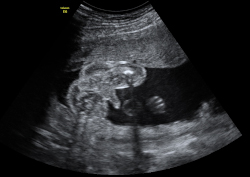

Esta ecografía 4D de la semana 20 de embarazo muestra que los bebés prácticamente empiezan a chuparse el dedo dentro del útero materno. El feto se acerca el dedo pulgar a la boca y en las imágenes finales la abre, muy probablemente para chupárselo.

En las imágenes del final, se puede apreciar cómo la criatura incluso abre la boca, quizá para chuparse el dedo pulgar. Es un reflejo el de succión que mantendrá fuera del útero, ya sea con su propio dedo o mediante la lactancia materna.